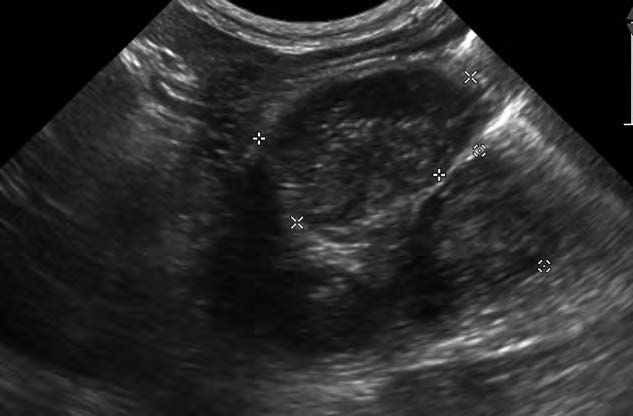

- 平滑肌瘤通常在靠近贲门处表现为离散的、表面光滑的肿块(图1)。

图1. 一只因呕吐和低血糖就诊的犬的胃部肿块的超声图像。该肿块呈分叶状、双叶形,从贲门沿小弯延伸至胃底,大小约为2.2×3.5厘米。肿块内有一个小的囊性区域。胃部扩张,充满大量气体和呈圆形的高回声阴影结构,符合食物残渣。